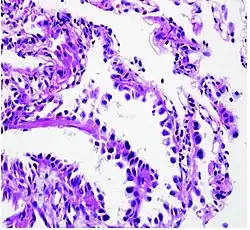

Histopathology

If possible, a biopsy of any suspected lung tumor is performed to make a microscopic evaluation of the cells involved and is ultimately required to confirm diagnosis.[7] Biopsy should be attempted in distant lesions first to establish a histologic diagnosis and to simultaneously confirm metastatic staging. The biopsy material is also used to analyze whether the tumor express any specific mutations suitable for targeted therapy (e.g. EGFR mutation or ALK mutation). Biopsy can be accomplished via bronchoscopy, transthoracic needle biopsy, and video-assisted thorascopic surgery (VATS).[4]

While sputum cytology has been shown to have limited utility, thoracentesis, or aspiration of pleural fluid with an ultrasound-guided needle, should be performed when pleural effusion is present. When malignant cells are identified in the pleural aspirate of patients highly suspect for lung cancer, a definitive diagnosis and staging (stage IV adenocarcinoma of the lung) is established.[4]

Adenocarcinoma of the lung tends to stain mucin positive as it is derived from the mucus-producing glands of the lungs. Similar to other adenocarcinoma, if this tumor is well differentiated (low grade) it will resemble the normal glandular structure. Poorly differentiated adenocarcinoma will not resemble the normal glands (high grade) and will be detected by seeing that they stain positive for mucin (which the glands produce). Adenocarcinoma can also be distinguished by staining for TTF-1, a cell marker for adenocarcinoma.[29]

As discussed previously, the category of adenocarcinoma includes are range of subtypes, and any one tumor tends to be heterogeneous in composition. Several major subtypes are currently recognized by the World Health Organization (WHO)[1] and the International Association for the Study of Lung Cancer (IASLC) / American Thoracic Society (ATS) / European Respiratory Society (ERS):[30][31][32] lepidic predominant adenocarcinoma, acinar predominant adenocarcinoma, papillary predominant adenocarcinoma, micropapillary predominant adenocarcinoma, solid predominant adenocarcinoma, and solid predominant with mucin production. In as many as 80% of these tumors, components of more than one subtype will be recognized. Surgically resected tumors should be classified by comprehensive histological subtyping, describing patterns of involvement in increments of 5%. The predominant histologic subtype is then used to classify the tumor overall.[2] The predominant subtype is prognostic for survival after complete resection.[33]

To reveal the adenocarcinomatous lineage of the solid variant, demonstration of intracellular mucin production may be performed. Foci of squamous metaplasia and dysplasia may be present in the epithelium proximal to adenocarcinomas, but these are not the precursor lesions for this tumor. Rather, the precursor of peripheral adenocarcinomas has been termed atypical adenomatous hyperplasia (AAH).[10] Microscopically, AAH is a well-demarcated focus of epithelial proliferation, containing cuboidal to low-columnar cells resembling club cells or type II pneumocytes.[10] These demonstrate various degrees of cytologic atypia, including hyperchromasia, pleomorphism, prominent nucleoli.[10] However, the atypia is not to the extent as seen in frank adenocarcinomas.[10] Lesions of AAH are monoclonal, and they share many of the molecular aberrations (like KRAS mutations) that are associated with adenocarcinomas.[10]

Signet ring and clear cell adenocarcinoma are no longer histological subtypes, but rather cytological features that can occur in tumour cells of multiple histological subtypes, most often solid adenocarcinoma.[30]